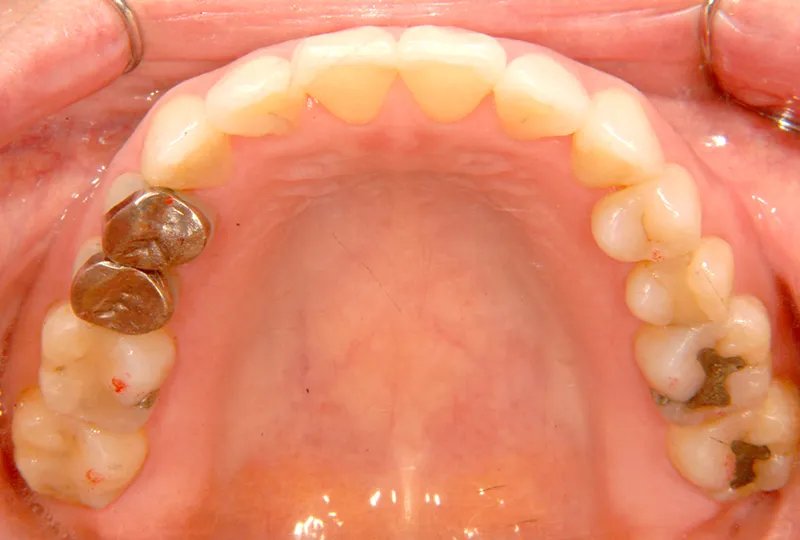

初診時年齢 40歳以上 (女性) 主訴 上下のがたがた・噛み合わない

診断名 叢生 装置名

特徴 ゆがんで生えている

状態 ガタガタ・でこぼこに生えている(叢生)

八重歯(叢生)

上下のがたがたと噛み合わない事を主訴に来院されました。

歯は抜かずに矯正治療しました。

初診